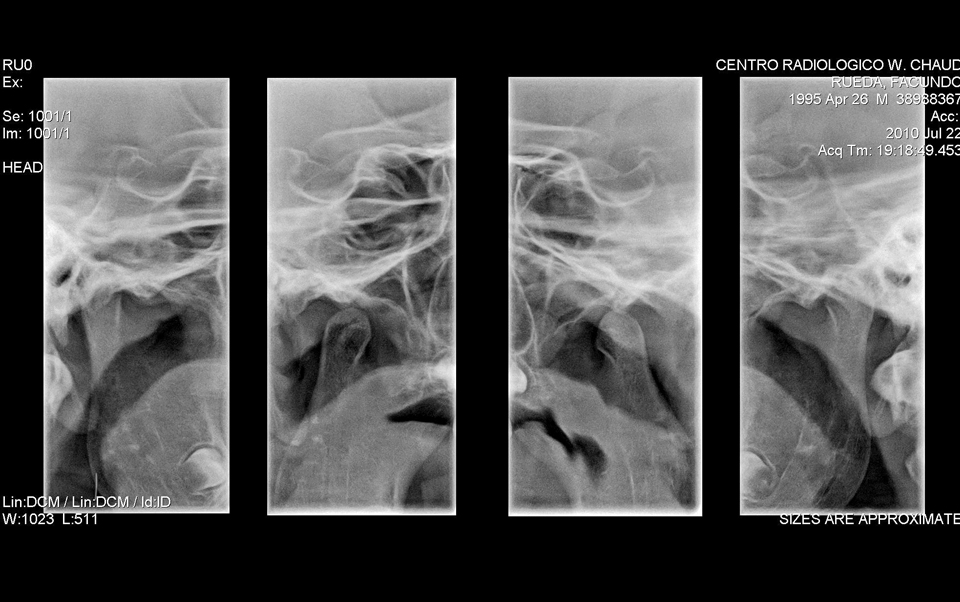

Estudio que permite evaluar de manera general el movimiento de la articulación témporo-mandibular y comparar bilateralmente, a boca abierta y cerrada, la posición condilar en una sola placa.